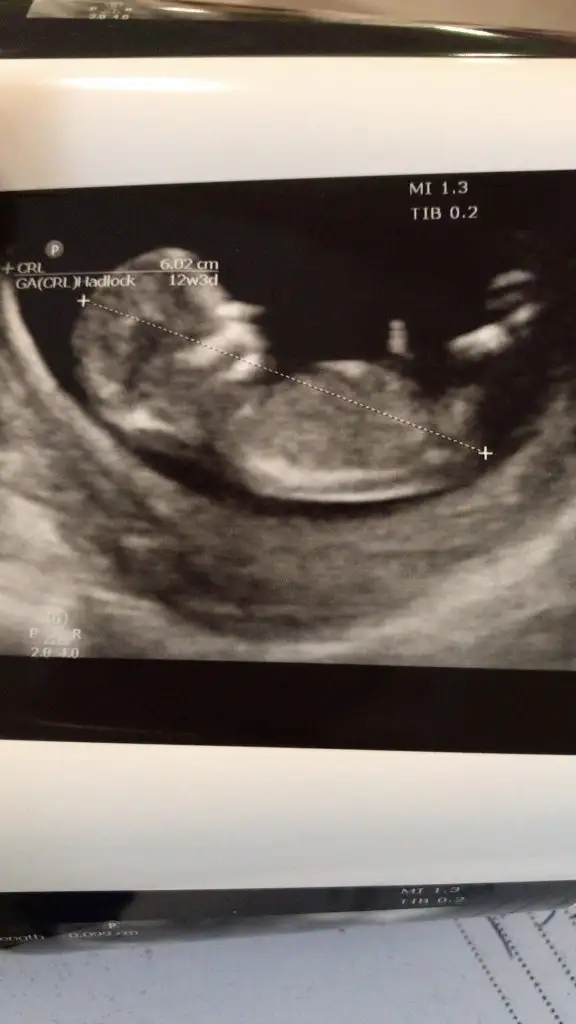

Bizede bi tahmin yapar mısınız ???

Günaydın Ikra meyra Ikra meyra 1 kızım bir oğlum var bakalım hangisinin yanına eş olcak 😊 11 de ki usg ye de erkek gibi demiştin ben hala anlamıyorum resimlerden bir şey kafa yapısına göre mi yoksa nub a göre mi yorumluyorsun , 1 ay sonra sonraki kontrolüm . Tekrar görürşürüz bakalım sonuçları bildiririm😘